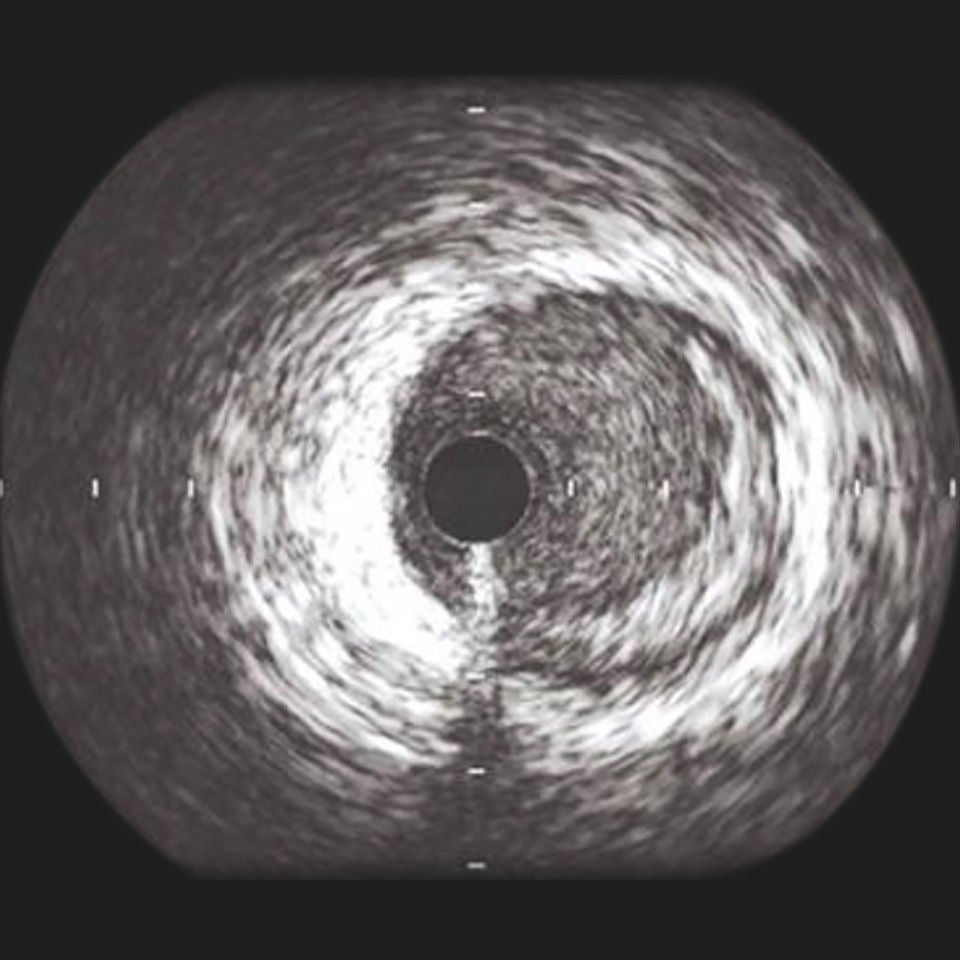

OPTICROSS HD Imaging Catheter 60MHz

IVUS image of inside a coronary vessel using the 60MHz Opticross catheter

Axial resolution: 22µm

High-Definition IVUS image quality helps physicians more accurately identify lesion length, assess plaque morphology, and determine the tools required for vessel prep. See how OPTICROSS HD’s 60 MHz images stack up against the competition.